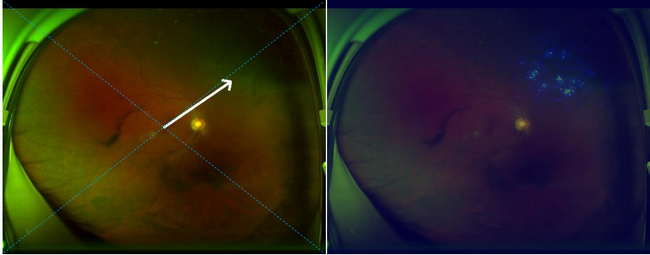

左侧图片箭头指处为视网膜脱离,右侧图片高亮区域热图提示视网膜脱离的精确位置

这款系统不仅能对眼底图像进行解读,同时可以自动标出病变部位,有助于医生有针对性的解读报告。同时如果视网膜脱离检查结果呈阳性,系统会自动给予体位指导,以延缓视网膜脱离的进展,降低手术并发症,改善患者的视力预后。